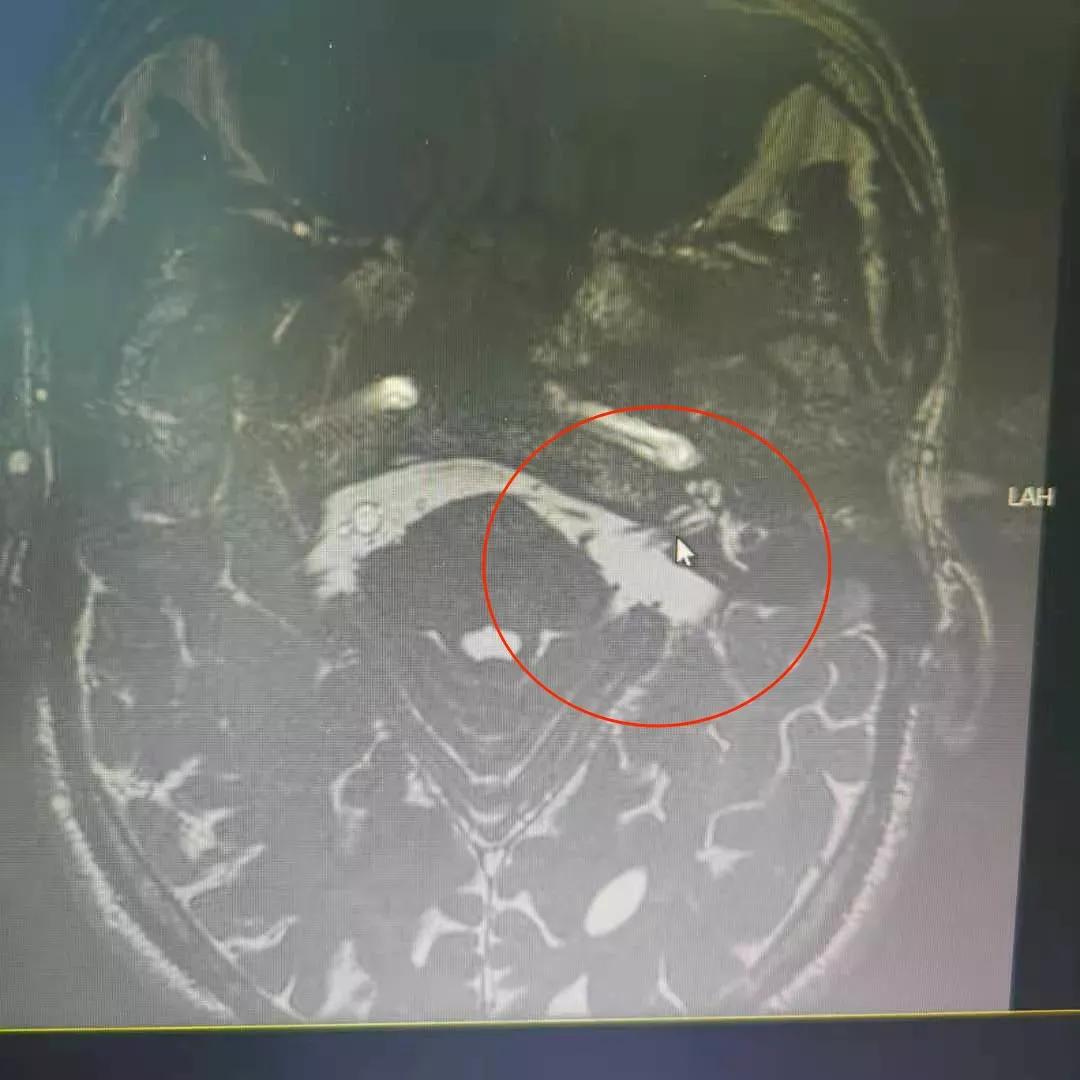

术前头颅MR上所示,三叉神经根部被小血管压迫

经过术前评估和充分准备后,手术开始了,我们在耳后做了一个5cm的小切口,再使用显微微钻和铣刀在颅骨上,开了一个2.0cm的骨瓣,剪开硬脑膜。在显微镜下找到压迫三叉神经的三根责任血管,将责任血管牵开,解除对三叉神经的压迫后,安置上Tefol绝缘垫片,缝合硬脑膜,回纳骨瓣,手术就做好了。